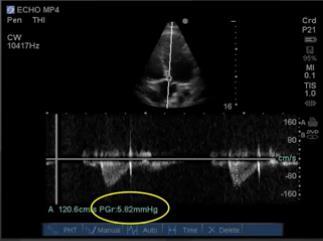

質的ドップラー – 脈波と連続波の画像